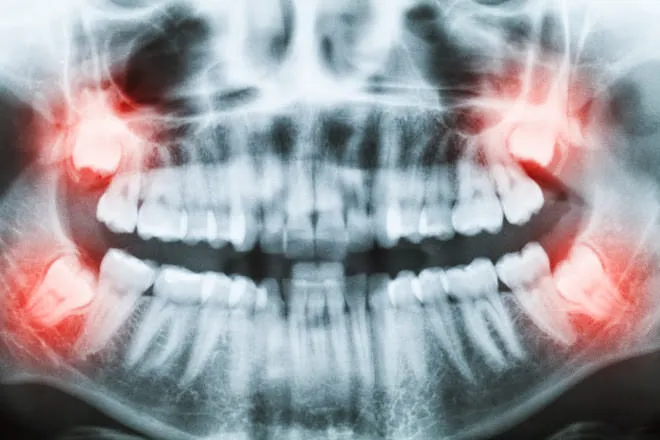

Na nossa clínica, a extração do siso é tratada com planejamento digital. Utilizamos radiografias panorâmicas e, quando necessário, tomografias computadorizadas para visualizar a posição exata das raízes e nervos.

Isso garante uma cirurgia extremamente rápida, segura e com o mínimo de trauma possível. Clique aqui e tire suas dúvidas sobre a cirurgia.